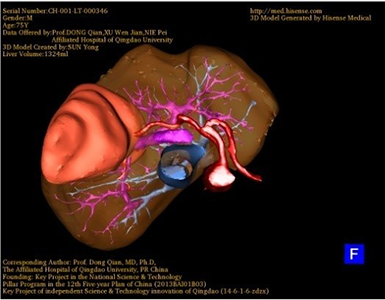

胆管细胞癌-CH-001-LT-000346

一般情况:CH-001-LT-000346,74岁男性患者。

将0.625mm双源薄层CT资料的静脉期和动脉期Dicom格式文件导入海信CAS系统。

通过调节窗宽窗位调整CT序号,对肿瘤,肝实质,胆囊,下腔静脉,肿瘤,肝动脉、门静脉及肝静脉等进行三维重建;系统自动计算肿瘤体积和肝脏体积。(图2—截图1---后链接截图2)

模拟手术操作,自动计算切除肿瘤体积。肝脏体积为1324ml,肿瘤体积为286.1ml,肿瘤体积为肝脏体积的21.6%,通过比对70-80岁正常肝脏体积为1118.08±190.14ml,通过术前模拟手术,精准判断切除后剩余肝脏体积能耐受,避免肝衰竭发生。术前手术方案的规划。

术前三维重建:

重建图片